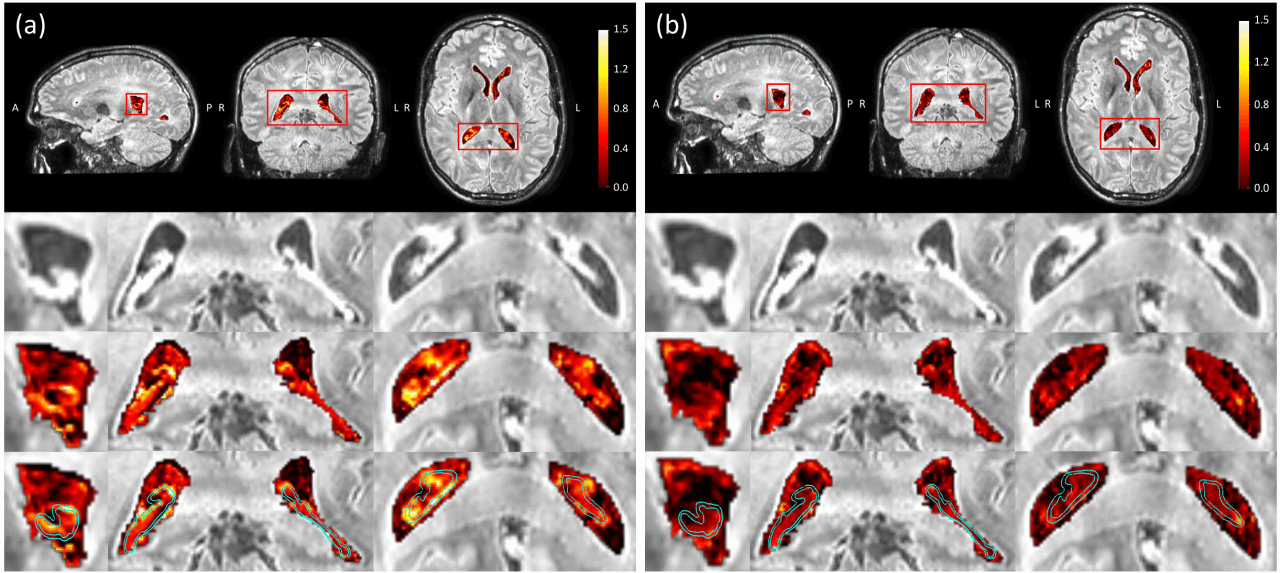

ad65c0d8227b5c767bf1ba70e07cce57.png

FLAIR MRI。

(a) 一名健康人类受试者在侧脑室(包括脉络丛,CP)给予钆基造影剂(GBCA)后代表性的ΔS/S(信号强度变化)图。第二行:GBCA后FLAIR图像。第三行:在侧脑室上叠加ΔS/S的FLAIR图像。第四行:脉络丛和过渡区域用青色轮廓线标记。

(b) GBCA后4小时的图。